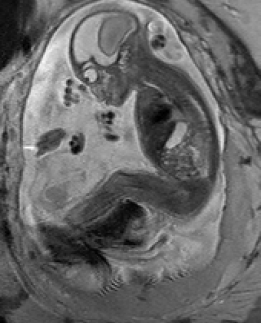

Reconstruction of Fetal Organs: Exemplary PVR and SVR reconstructions under motion introduced by kicking of the fetus are shown in Fig. 11. PVR reconstruction results show an improved visual appearance and less blurring in the region with severe motion artifacts (arrow). An example of a challenging clinical case with a kidney malformation in one of twin fetuses, is shown in Fig. 8. Our clinical partners confirmed that such complications are easier to examine and to quantify after PVR-based reconstruction.

(a) Input

(b) SVR

(c) PVR

Comparative experiments of PVR variants were carried out on 32 fetal MR scans at gestational ages of approximately 20 weeks, presenting with challenging image corruption. Tab. I (a) & (b) show numerical results of evaluating individual stacks before reconstruction (baseline), and the final reconstructed image using square patches, superpixels and multi-scale variants of PVR. Statistical testing between baseline and PVR variants was carried out using paired T-Tests and differences between using fixed or multi-scale and using square patches or superpixels were assessed via Two-factor ANOVA with repeated measures. In Tab. I (a) & (b) the names of PVR variants are marked in bold if statistically significant differences have been found during analysis, i.e., FS and MS and/or Square Patches and Superpixel pairs are bold if the results between them differ significantly.